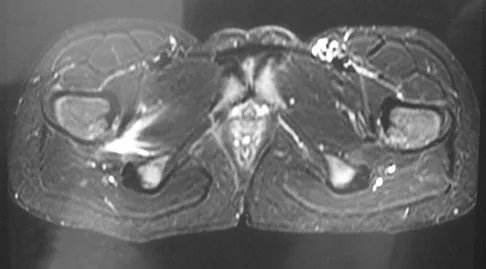

A 15-year-old girl who swims the breaststroke has had hip pain after training excessively for a national level competition. Based on the MRI scans shown in Figures 5a through 5c, what is the most likely diagnosis?

Explanation

The MRI scans reveal open physes but no evidence of a slipped capital femoral epiphysis, labral tear, or acetabular dysplasia. The femoral neck does not show evidence of a fracture. The muscle tear seen on the right side lies near the musculotendinous junction of the external rotators of the hip at the level of the lesser trochanter, representing the obturator externus. This is consistent with the forced motion required for the breaststroke kick. Grote K, Lincoln TL, Gamble JG: Hip adductor injury in competitive swimmers. Am J Sports Med 2004;32:104-108.